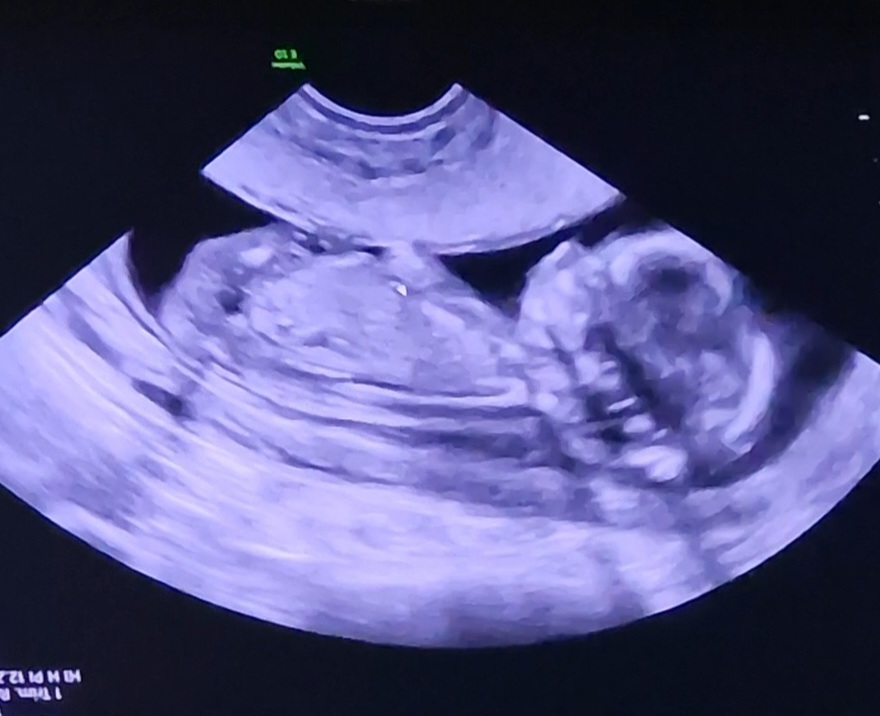

13+1

nå ble jo det meste sjekka I forrige uke, men litt nøyere denne gangen og ingenting å påpeke nå heller! Alt er tipp topp, og det er mest sansynlig en lillebror

Ble ikke så gode bilder denne gangen, da lille ligger langt nede, har bakovervendt livmor (og en del ekstra på kroppen) så innvendig ul ga best innsyn, men der begynner lille å bli litt stor også

Var 12+5 idag,men lille ble målt til 13+1, og termin ble satt til 30/5, får ikke det til å stemme annet enn at dataen regner 40+0 og ikke 40+3, så tror jeg holder på 2/6 frem til oul 28/12, selvom termin egentlig ble satt idag